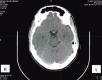

Traumatic brain injury (TBI) is a major cause of lifelong disability and death worldwide. Sport-related traumatic brain injury is an important public health concern. The purpose of this review was to highlight the importance of sport-related concussions. Concussion refers to a transient alteration in consciousness induced by external biomechanical forces transmitted directly or indirectly to the brain. It is a common, although most likely underreported, condition. Contact sports such as American football, rugby, soccer, boxing, basketball and hockey are associated with a relatively high prevalence of concussion. Various factors may be associated with a greater risk of sport-related concussion, such as age, sex, sport played, level of sport played and equipment used. Physical complaints (headache, fatigue, dizziness), behavioral changes (depression, anxiety, irritability) and cognitive impairment are very common after a concussion. The risk of premature return to activities includes the prolongation of post-concussive symptoms and increased risk of concussion recurrence.